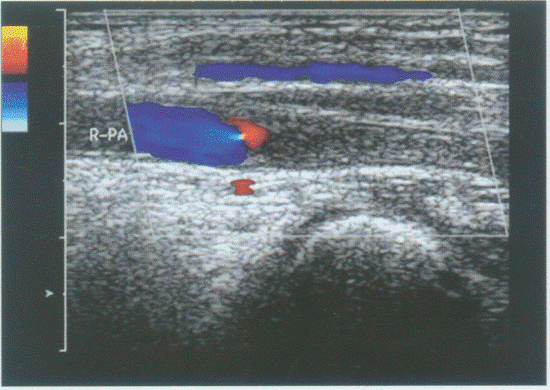

C.大脑后动脉